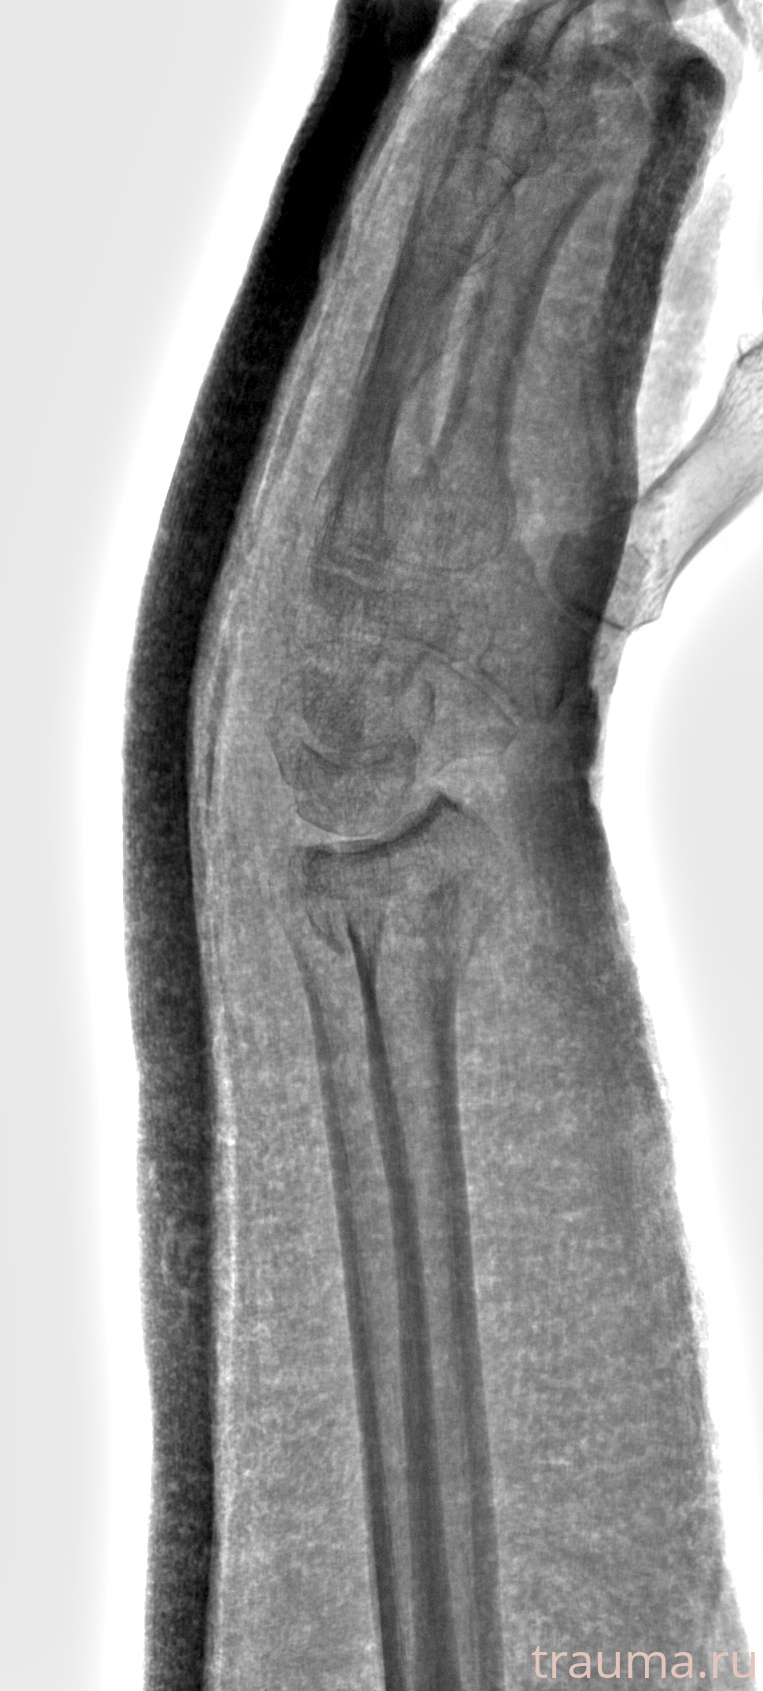

Рентгенограммы

Рентген на дому: по вашему адресу приезжает врач-рентгенолог, травматолог-ортопед с мобильным рентгеновским аппаратом, проводит диагностику травмы или заболевания, делает необходимые рентгенограммы, дает рекомендации по дальнейшему лечению. Получить качественные снимки в домашних условиях возможно благодаря уникальной методике, разработанной МосРентген Центром для института  Склифосовского